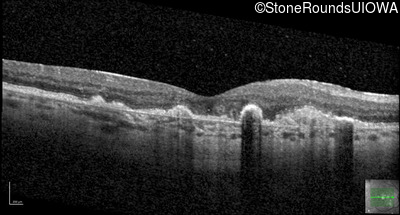

Malattia Leventinese (IIJ)

Malattia Leventinese (IIJ)

This 43 year old woman has experienced a gradual reduction in her central vision for the past 3 years.

| Malattia Leventinese | EFEMP1 | Arg345Trp CGG>TGG | AD |